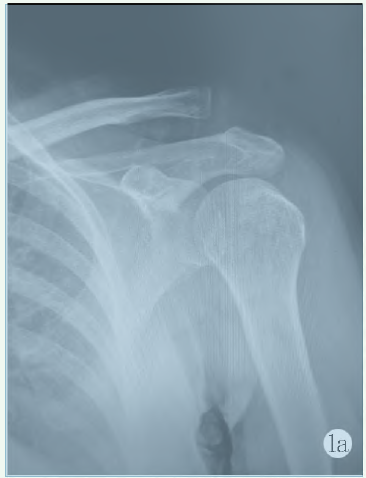

患者入院后,完善常規(guī)檢查,排除手術禁忌證,患肢以肩頸腕托帶進行妥善外固定。如果患肢腫脹比較明顯,可以予以適量甘露醇,加以局部冰敷治療。所有患者均完善肩關節(jié)正側位X線及三維CT重建檢查明確診斷為肩鎖關節(jié)脫位(圖1a)。術前體格檢查確認上肢運動感覺功能情況。

圖1 患者,男,60 歲,左肩外傷后疼痛,活動受限

1a: 術前正位X 線片,顯示Tossy III 型肩鎖關節(jié)脫位